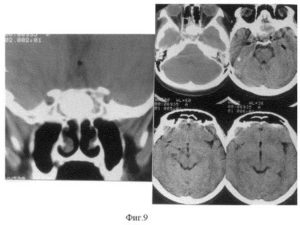

Одна из них — КТ-цистернография. При люмбальной пункции в подоболочечное пространство спинного мозга вводят низкоосмолярные неионные рентгеноконтрастные вещества (омнипак, ультравист, йопомиро).

После экспозиции больного в течение 40 мин — 1 час с возвышенным положением ножного конца (угол 30 градусов) выполняют КТ головного мозга, которая выявляет и костный дефект и ликворную фистулу, через которую истекает ЦСЖ с диффундированным в ней рентгеноконтрастным веществом (симптом «ликворной дорожки»).